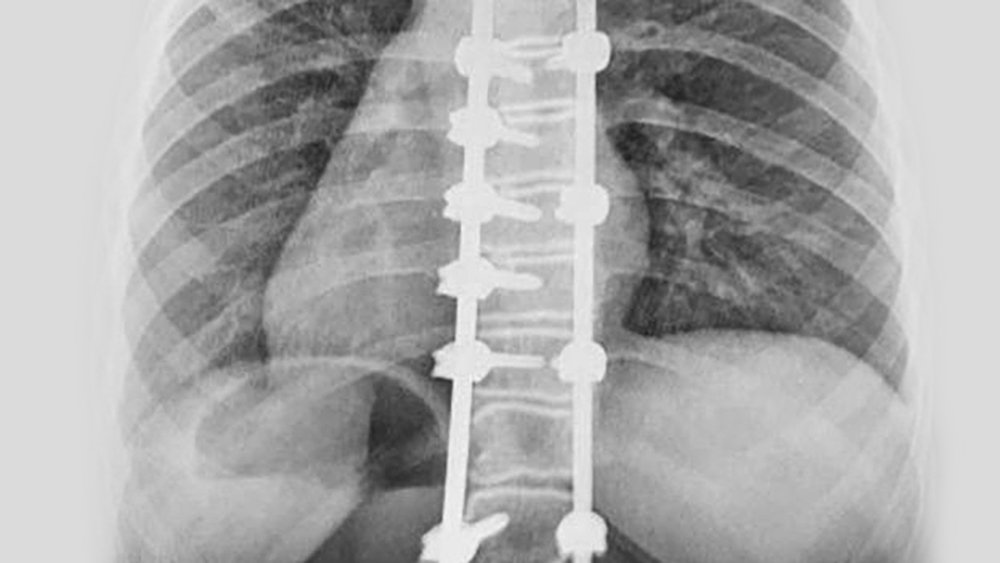

La piattaforma Ennovate® rappresenta una soluzione tecnologicamente avanzata che sfrutta le esperienze chirurgiche e cliniche. Dal tratto della colonna cervicale a quello sacropelvico, Ennovate® migliora la modularità intraoperatoria, adattandosi alle diverse esigenze.

Ispirato all'anatomia umana e alla clinica Ennovate® TLSP è versatile e modulare per soddisfare le tue esigenze individuali.

Per saperne di più su Ennovate® TLSPEnnovate® avendo un' ampia gamma di soluzioni per il trattamento della colonna vertebrale posteriore con un'unica piattaforma, con un grande vantaggio per la struttura ospedaliera. Grazie al design completamente modulare, i moduli di strumenti e impianti possono essere adattati in modo specifico alle esigenze dell'oespedale. Si evitano, quindi, grandi quantità di strumentari in sala operatoria, si ottimizzano le procedure, si aumenta l'efficienza nei processi e si ha un impatto economico positivo.

Le tecnologie di navigazione stanno aprendo nuove strade nella chirurgia della colonna vertebrale verso orizzonti inaspettati. Ennovate® unisce la piattaforma spinale più avanzata fornita da AESCULAP® con tecnologie di navigazione all'avanguardia, portando i trattamenti spinali a un livello molto avanzato. Grazie alle moderne tecnologie di chirurgia computerizzata (CAS), il posizionamento delle viti peduncolari diventa più affidabile, accurato e sicuro.